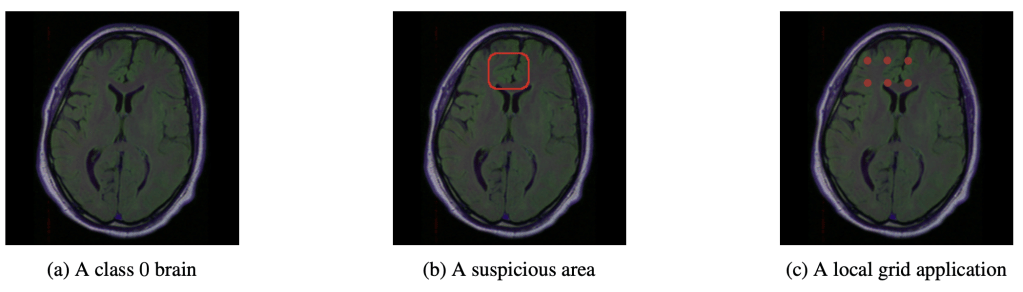

Continue reading →: Explanations of AbsenceExplainable AI is any process in which we try to identify which features a model used in making a particular prediction. But what happens when we want to explain something that is defined by the absence of features? A model may learn that certain pixel characteristics are associated with a…